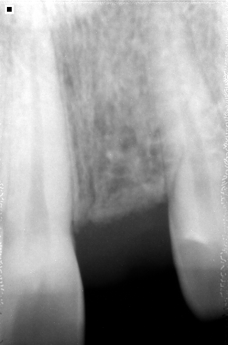

El proceso de utilizar implantes inicia con un completo examen clínico y por imágenes de nuestros pacientes para determinar el estado de salud bucal y dental (dientes, encías, hueso alveolar, etc.) y salud en general con el fin de obtener un diagnóstico y plan de tratamiento seguro, cómodo y duradero.

Reemplazamos la pieza dental original por una fabricada en Titanio biocompatible que se introduce en el hueso de la mandíbula, sobre ésta nueva raíz se fija una pieza de metal y cerámica (corona) resistente que se iguala en color y forma con el fin de brindar un aspecto lo más natural posible.